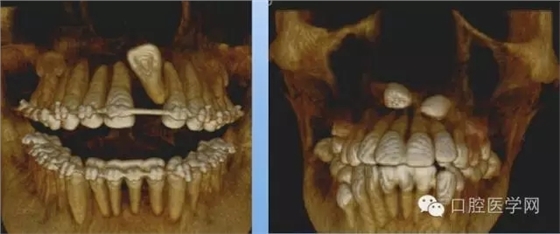

額外牙

X線表現(xiàn):最多見于上頜兩中切牙之間;圓錐形,根短小;拍攝X線片可確定額外牙的數(shù)目、位置、形態(tài)與鄰牙的關(guān)系。